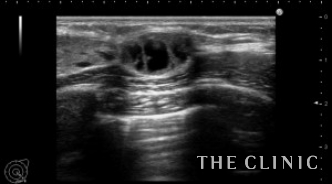

ベイザーで崩しているところです。